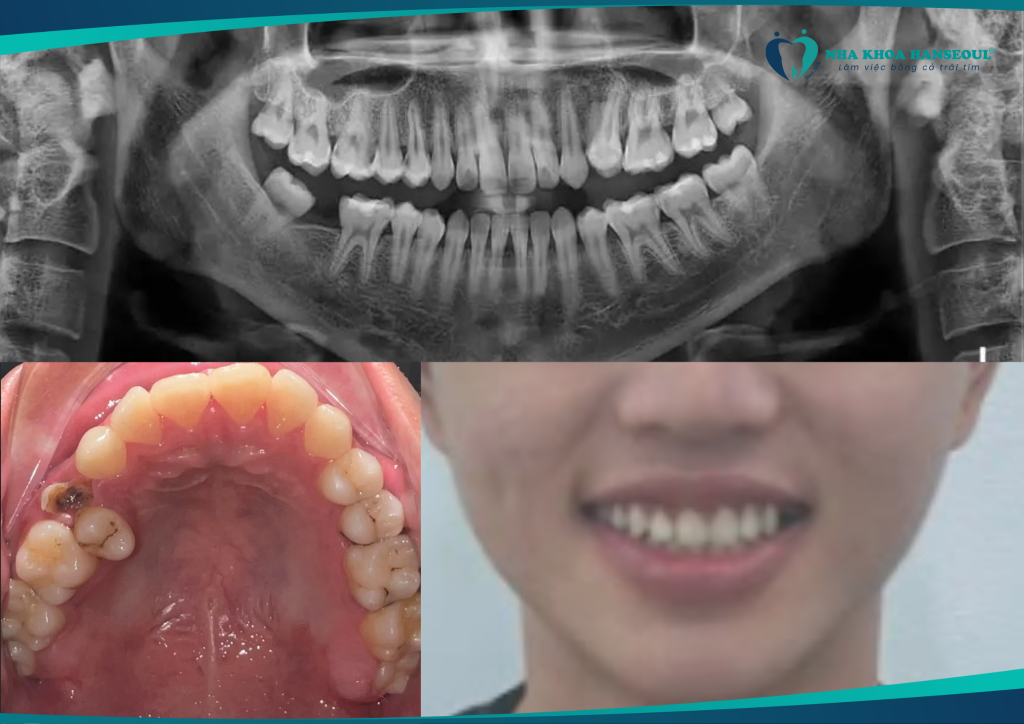

1 Tình trạng răng của Chí Tâm trước khi niềng

Bạn Nguyễn Chí Tâm, sinh năm 2004, là sinh viên Trường Đại học Văn hóa TP. Hồ Chí Minh. Vốn là người năng động và yêu thích sự hoàn thiện bản thân, việc gặp phải một số khiếm khiếp về răng miệng đã từng là rào cản lớn khiến Tâm cảm thấy tự ti trong giao tiếp và học tập.

Cụ thể, Chí Tâm gặp phải tình trạng:

- Lệch nhân trung dẫn đến lệch khớp cắn tổng thể

- Mất răng số 47

- Sâu răng nhiều vị trí

- Hàm răng không đều, ảnh hưởng thẩm mỹ và chức năng nhai

Đây là tình trạng điển hình của khớp cắn lệch. Khiến gương mặt không cân đối và cản trở phát âm, ăn nhai. Việc lựa chọn niềng răng là cách duy nhất để khắc phục một cách toàn diện và lâu dài.